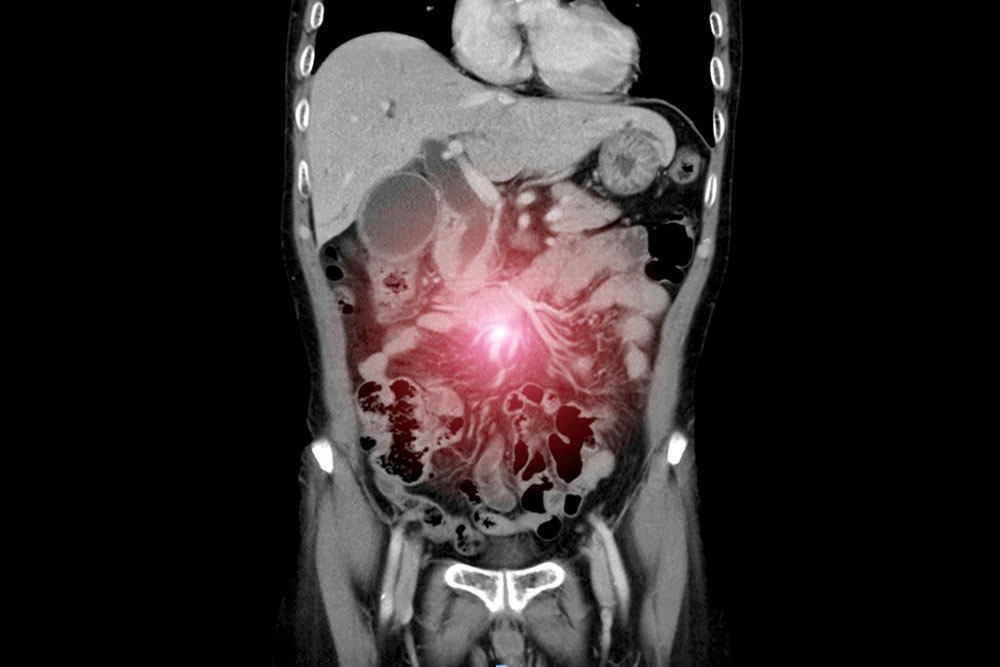

Peritoneal cancer surgery

Cytoreductive surgery aims to remove all visible tumor deposits from the peritoneal surfaces and affected organs. This may involve multi-organ resections and meticulous stripping of tumor-bearing peritoneum. The success of this procedure lies in achieving minimal residual disease, which directly correlates with long-term survival.